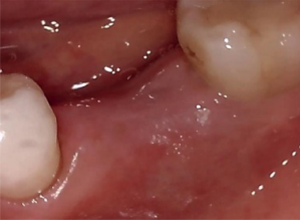

50代 女性 前歯 インプラント抜歯即時・GBR

| 年代・性別 | 50代・女性 |

|---|---|

| 主訴 | 歯の根っこが折れているため、抜歯が必要になり、その後インプラント治療を希望された。 |

| 部位 | 左上1 |

| 治療期間 | 8ヶ月 |

| 費用 | ¥484,000(税込) |

| 副作用・リスク |

|